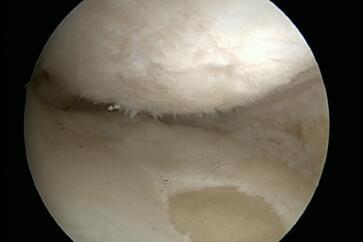

Cartilage damage

Unfortunately, cartilage injuries mostly affect young and active patients, so the demand on the therapy and the results are very high. However, the articular cartilage is not supplied with blood and has no nerve supply. It is nourished by diffusion from the synovial fluid and the adjacent bone. Therefore, cartilage injuries do not show a sufficient healing tendency, initial injuries can lead to joint wear. Surgical measures have a long post-treatment period, and often only a low load is allowed on the limb in order to achieve sufficient stability of the regeneration. Instabilities, axial defects, and ligament injuries of the knee joint must always be treated as well. Various therapy options are available to us for the treatment of cartilage injuries.

All therapy options have a specific field of application, and different risks and complications. Thus, the stage, size, and location of the cartilage injury determine the choice of procedure. Many of the procedures lead to the formation of so-called fibrocartilaginous replacement tissue rather than hyaline articular cartilage, but these therapies do show good medium-term clinical results. With bone-cartilage transplantation and cartilage cell cultivation, we also have procedures available that can lead to hyaline regeneration of the defect. So before the therapy, the damage must be diagnosed. Size and depth then determine the therapy. Simplified, this means that grade I/II damage is treated nonoperatively, i.e. conservatively, and grade III/IV damage is treated surgically. The size of the damage then comes into play in the choice of procedure. Damage <2.5 cm² is treated with microfracturing/nano drilling. In the case of very deep damage, a bone cartilage cylinder can also be used. Damage >2.5 cm² is treated with matrix-induced chondrogenesis or autologous chondrocyte transplantation. New procedures are constantly coming onto the market for the treatment of cartilage damage.